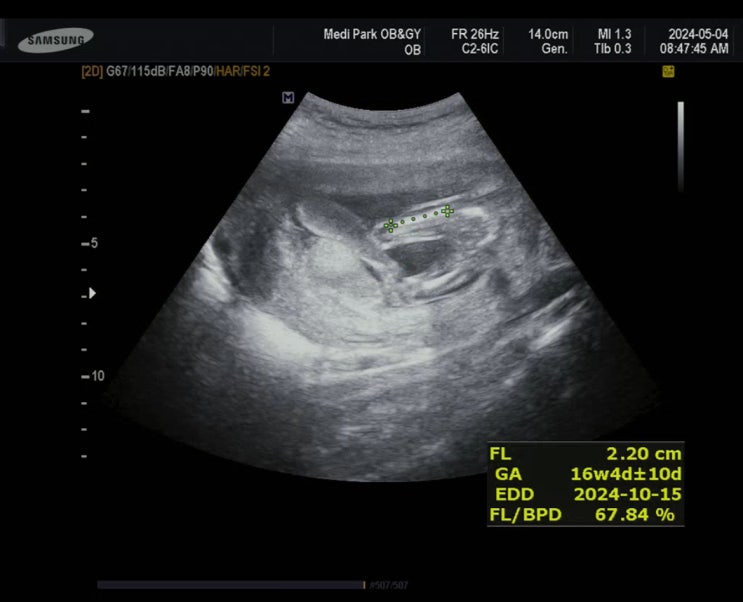

레몬크기만 해진 용용이 배가 볼록하게 나와서는 고무줄 바지, 고무줄치마, 원피스만 입는다 고기는 당최 ...

그동안 받았던 검사들 정리 겸 검사들을 왜 받는지, 제가 다니는 산부인과에서는 어떤 검사를 추가로 시행...